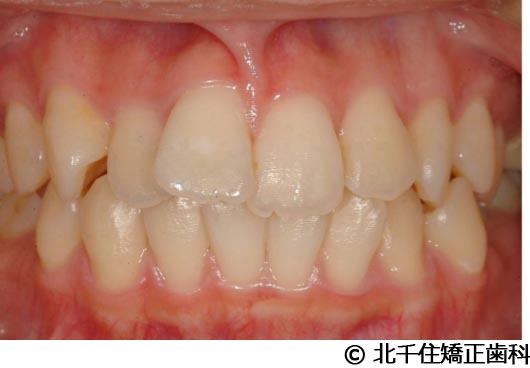

【症例3】叢生

- 治療前

- 治療後

- 治療名

- 叢生

- 費用

- 1,125,000円(税込)

- 期間

- 2年1ヵ月

- 治療回数

- 26回

- 通院頻度

- 1ヵ月ごと

- 年齢・性別

- 19歳3ヵ月・女性(初診時)

治療内容

-

患者様の症状

主訴:デコボコ、口元の突出

治療方法

上下顎第一小臼歯4本を抜歯してワイヤー矯正(セラミックブラケット)。

治療結果

叢生に対し抜歯を併用した矯正治療により、歯列および咬合関係の調整を行った症例である。治療後は保定装置を使用し、歯列および咬合の安定維持を目的として定期的な経過観察を行っている。

※治療結果は個人差があります。

治療を行う上での注意点(リスク・副作用)

歯磨き不良に伴うカリエスや歯周病、歯根吸収など。